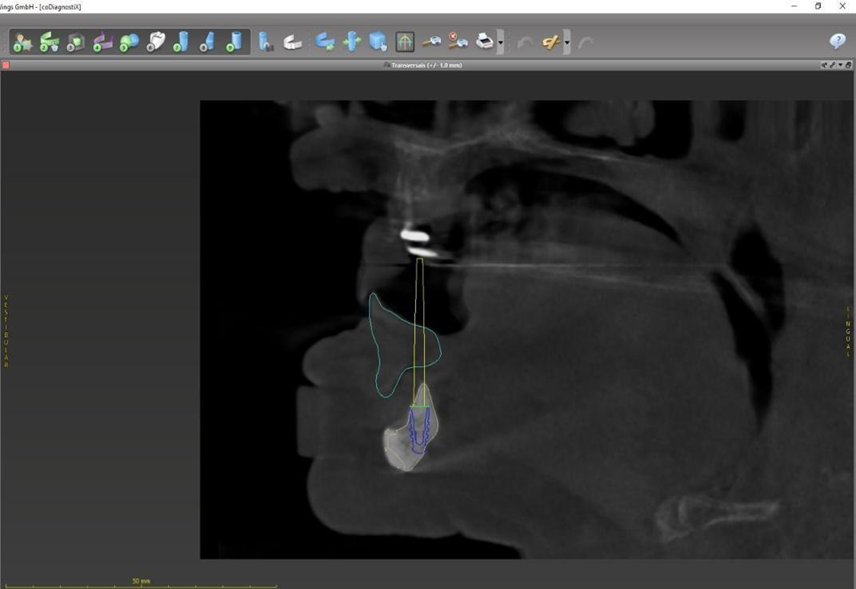

Paciente de 62 anos, do sexo feminino, sem comorbidades e história médica pregressa, apresentava severa reabsorção óssea em regiões anteriores e posteriores da mandíbula devido a uma peri-implantite (Figuras 1A e 1B). Feita a remoção dos implantes, a paciente optou por utilizar uma prótese total mucossuportada até a nova intervenção com prótese do tipo protocolo inferior. Após seis meses, a mandíbula encontrava-se cicatrizada (Figura 2). Como parte do protocolo diagnóstico, foi realizada tomografia computadorizada pela técnica do duplo DICOM. Com a severa perda óssea em região anterior de mandíbula, optamos por realizar a cirurgia de forma guiada, aumentando a previsibilidade e precisão da cirurgia. Os arquivos obtidos foram exportados para o software CoDiagnostiX, possibilitando a realização do planejamento reverso e o subsequente posicionamento virtual dos implantes (Figura 3). Com base no planejamento, optou-se pela instalação de quatro implantes Implacil Osstem CM AR Due Cone (3,5 x 7 mm), associados a mini-cônicos de 1,5 mm (Figuras 4A, 4B, 4C, 4D e 4E). A partir da tomografia da prótese da própria paciente, confeccionaram-se duas guias cirúrgicas: uma guia de pino de fixação (Figura 5) e uma guia de fresagem para a instalação dos implantes (Figura 6). Durante o procedimento cirúrgico, inicialmente foi posicionada a guia de pino de fixação para fresagem dos pinos de fixação e orientação da sequência cirúrgica (Figura 7). Após essa etapa, a guia foi substituída pela guia de fresagem dos implantes (Figura 8), utilizada para a fresagem e inserção dos implantes planejados (Figura 9). Concluída a instalação, optou-se por seguir o fluxo analógico, com a adaptação dos mini-cônicos 1.5 mm (Figura 10), realização da transferência de moldagem com silicona de adição leve e sutura com fio absorvível Vycril 6-0. O guia inicial foi adaptado com broca Maxicut, possibilitando sua utilização como molde de orientação para o laboratório protético (Figura 11). Após a moldagem, foram posicionadas as tampas de proteção sobre os implantes. Na fase protética, transcorridas 48 horas do procedimento cirúrgico, foi realizada a prova clínica da barra metálica e dos dentes (Figura 12). Na etapa subsequente, 72 horas após a cirurgia, procedeu-se à instalação e entrega do protocolo mandibular inferior e radiografia prévia, reabilitando funcional e esteticamente a paciente em curto espaço de tempo (Figuras 13A e 13B).